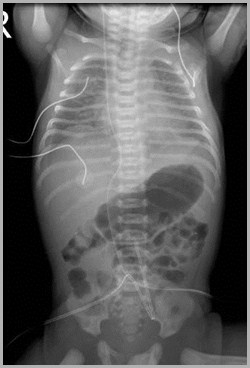

Two UACs, one at T7, the other at L3UVC in portal vein

T7

L3